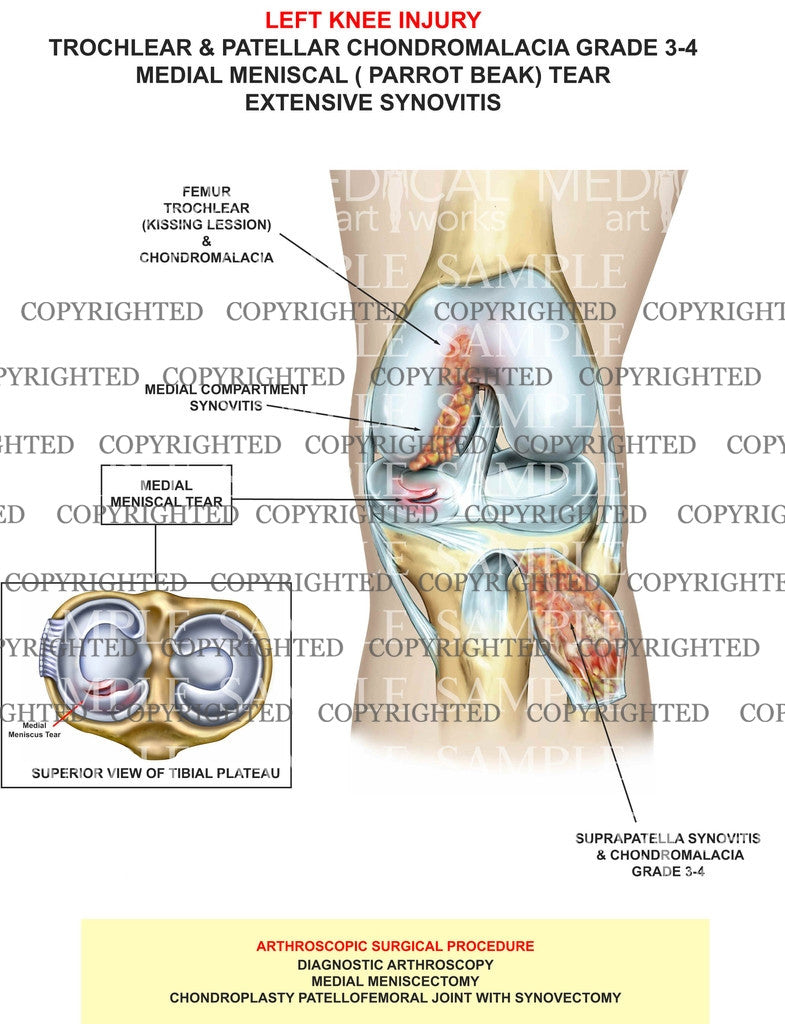

Trochlear & Patellar Chondromalacia

Trochlear & Patellar Chondromalacia

Trochlear & Patellar Chondromalacia grade 3-4

medial meniscal ( parrot beak) Tear

extensive Synovitis